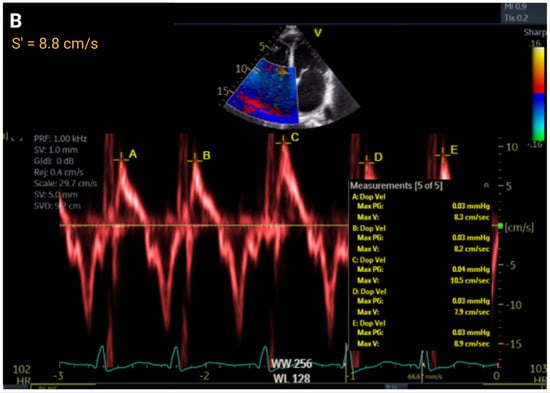

| S′, cm/s | >9.5 | ≤9.5 to ≥7.2 | ≤7.2 to >5.0 | ≤5 | r = 0.36 to 0.52 | |